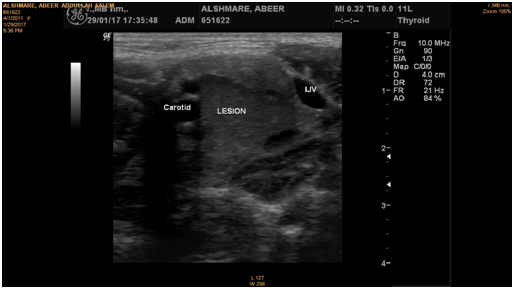

Figure 8 Ultrasound of the neck shows large heterogeneous lesion.

Figure 9 Ultrasound of the neck shows large heterogeneous lesion which is seen in the anterior triangle of a left cervical region, between the internal jugular vein and the carotid artery, displacing the carotid anteromedially and the jugular posteriorly; it measured about 3x1.5x1.5cm, it shows heterogeneous hypervascular texture with focal calcification. For clinical correlation and further investigation considering Carotid Space masses (paraganglioma, chwannoma, others).